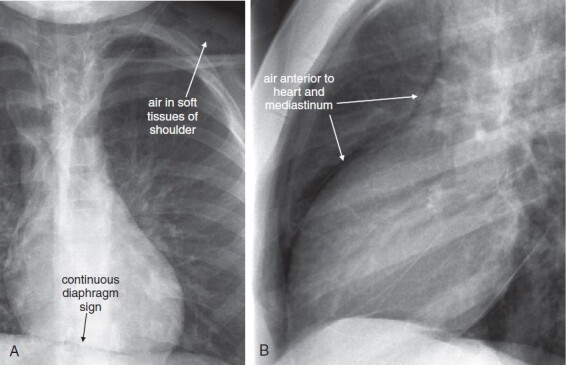

In an upright patient, air within the peritoneal cavity collects beneath the diaphragm, making it visible on x-ray because of the contrast between the density of air and diaphragmatic soft tissue. (Figure 5-11, Figure 5-12, Figure 5-13, Figure 5-14 ). In a supine patient, air within the peritoneal cavity may collect in the midline anterior abdomen rather than in a subdiaphragmatic position and in addition will spread in the same horizontal plane as the x-ray detector beneath the patient, preventing the air from being visible. An x-ray obtained with an upright patient position is therefore more sensitive for detection of pneumoperitoneum.

Free air (pneumoperitoneum) can be recognized on upright chest x-ray. This finding relies on the silhouette sign described later in this chapter (see Figure 5-26): air density is readily seen when in direct contact with water (soft-tissue) density. A, The normal appearance of the upright chest x-ray in the absence of pneumoperitoneum. B, The appearance of the upright chest x-ray in the presence of pneumoperitoneum. On an upright chest x-ray, normally the inferior surface of the right diaphragm is not seen, as the liver (water or soft-tissue density) is in direct contact with the inferior border of the diaphragm (also water density). When air is present within the peritoneal cavity, it may collect inferior to the right diaphragm, superior to the liver. This air may be recognized as a black line or collection, making the inferior border of the diaphragm visible. On the patient’s left side, the normal gastric air bubble can simulate intraperitoneal air, as it is normal for the stomach to contain air. Fortunately, usually the gastric wall and adjacent diaphragm are thicker than the diaphragm alone would be, allowing the normal gastric bubble to be distinguished from subdiaphragmic pneumoperitoneum. In some cases, pneumoperitoneum may extend beneath the central diaphragm, in which case the inferior border of the heart may be partially visible. Normally, the heart, diaphragm, and liver are in contact, with no visible line separating them. Compare with Figure 5-12, Figure 5-14.

Figure 5-12.

Pneumoperitoneum is a critical finding requiring recognition on chest x-ray. Occasionally, it may be an unanticipated finding on chest x-ray in a patient who cannot provide an adequate history. Remember that normally the inferior surface of the diaphragm cannot be seen, as it is contiguous with a solid organ sharing the same water density on chest x-ray: the liver on the right, the spleen on the left. On the left, the interior surface of the stomach may be shown in relief by air within it. It may be difficult to distinguish this inner surface of the stomach from the inferior surface of the diaphragm, although the diaphragm alone should be thinner than the combined thickness of diaphragm and stomach. Within the abdomen, the external surface of the bowel wall should not be seen, again because of its contiguity with other soft-tissue structures. Air within the bowel is readily seen and makes the internal surface of the bowel wall quite apparent. When pneumoperitoneum exists, the external surface of the bowel can be seen. A normal finding that may simulate this is the presence of two adjacent loops of bowel with their walls abutting. In this case, the internal surface of both walls may be seen, and it may appear that air is present on both sides of the wall of a single loop. In A (upright PA x-ray) and B (upright lateral x-ray), copious free air is present. A, Both diaphragms are outlined, and several bowel loops can be seen with air on both sides of their walls. B, The lateral x-ray also demonstrates this finding. Compare with the CT from the same patient in Figure 5-13.